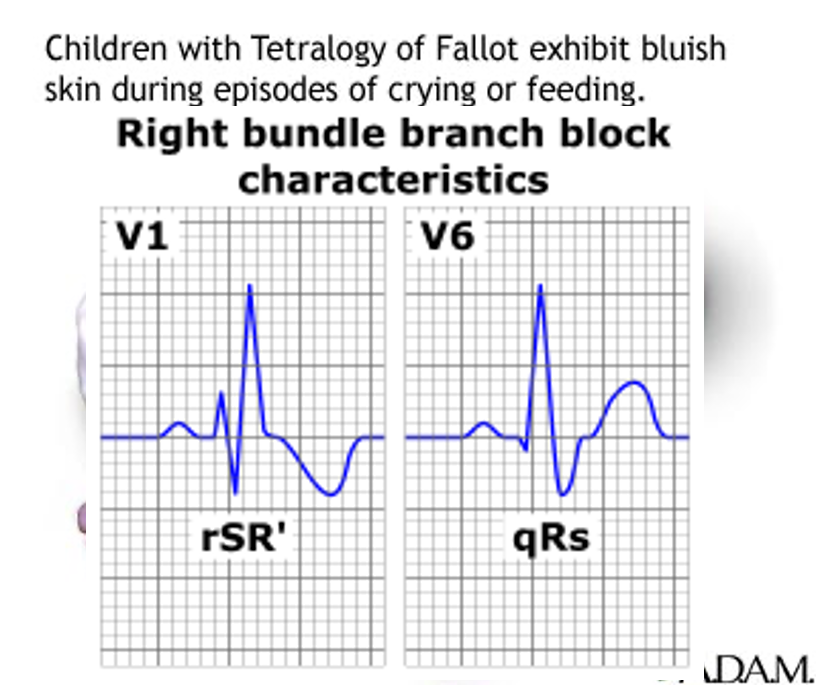

Tetralogy of Fallot

TOF is the most common cyanotic congenital heart defect. ~10%.

Cyanosis pulmonary stenosis.

A pulmonary stenosis murmur.

A single S2 and right ventricular impulse at LSB.

Hypoxic (Tet) spells: - Hyperpnea occurs with gradually increasing cyanosis and loss of the murmur. - Prolonged unconsciousness and convulsions, - hemiparesis, or death may occur.

Tetralogy of Fallot

- “Tet spell”

- Hyperpnea

- Worsening cyanosis

- Disappearance of murmur

- RBBB pattern on ECG